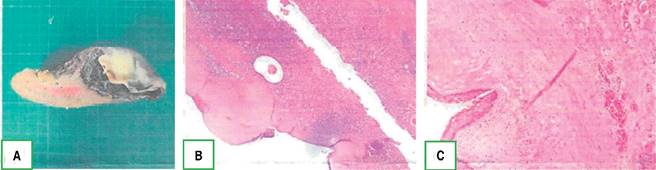

En el reporte histopatológico se describe bazo de 15 × 6 × 5 cm con quiste epidermoide (epitelio escamoso estratificado no queratinizante) de 8 cm con superficie interna trabeculada (Figura 6).

Figura 6: A) Espécimen de esplenectomía de 15 x 6 x 5 cm, peso de 167.5 gramos, con formación quística en un extremo de 8 cm de diámetro con superficie interna trabeculada. B-C) Formación quística con una cápsula fibrosa gruesa y una superficie interna tapizada por epitelio escamoso estratificado no queratinizante sin atipia. El parénquima presenta una pulpa roja con sinusoides con cambios por lisis. Pulpa blanca formada por folículos linfoides secundarios sin atipia.